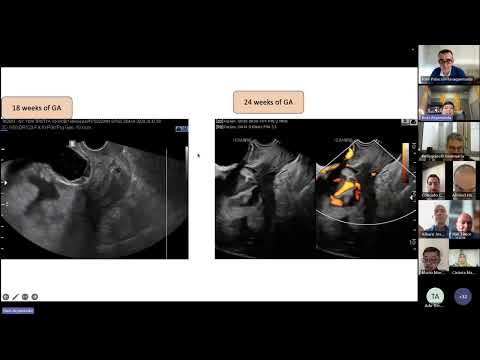

@RoziAryananda @nareswariCIN Now available on Youtube. Scarry US images but really upper anterior #accreta (type 1) good candidate for uterine sparing surgery. Thanks @RoziAryananda